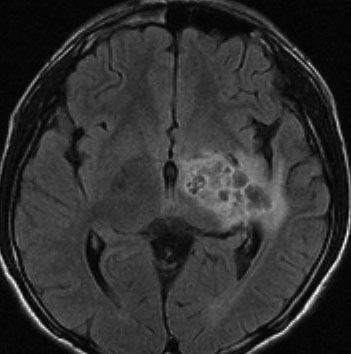

悪性神経膠腫と間違えそうなジャーミノーマ

14歳で右の片麻痺と学力の低下で発症しました。ガドリニウム造影がまだらで最初は膠芽腫かな?と思いましたが,mass effectが軽いことが解ります。geminomaとしては珍しいのですがperifocal edemaがあります。

定位生検術で病理組織診断をして化学療法を加えた後の画像です。germinomaのお約束どおり,化学療法できれいに消失します。ちょっとした小さな増強される部分が残るのですがこれはstromal reaction (gliofibrosis)をみているので,残存腫瘍ではありません。余分な追加の放射線治療をしないように気をつけます。